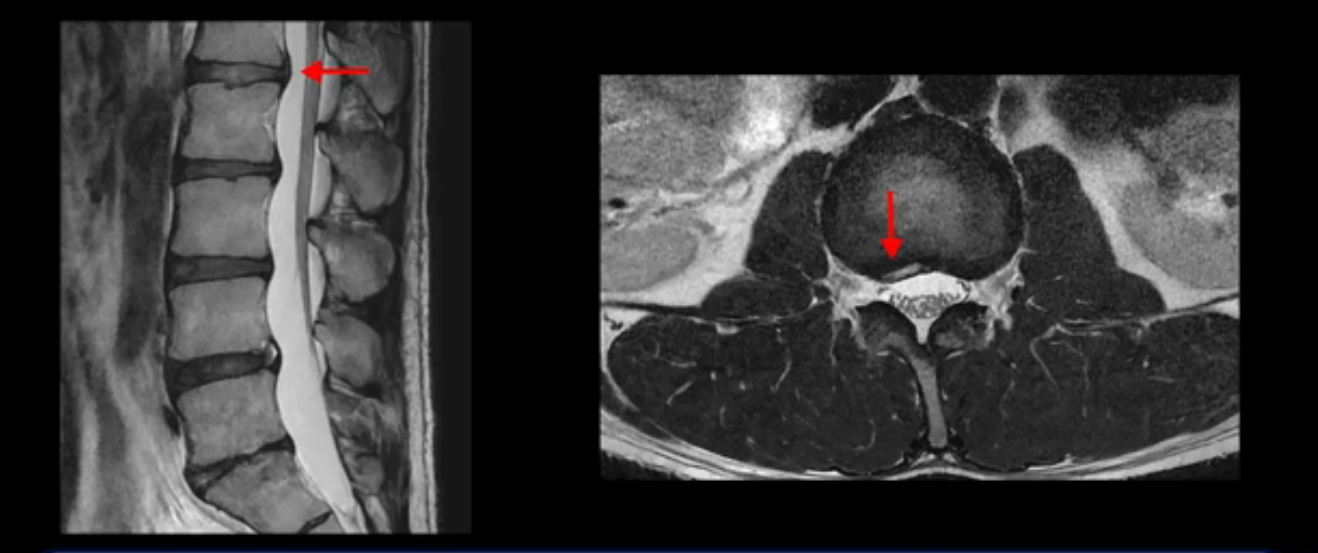

그런데 이분의 증상과 MRI가 전혀 일치하지 않는데, 왜 그런지 지금부터 자세히 설명드립니다. 이분 증상은 앉으면 엉치와 허리가 심하게 아파 10분 이상 앉는 게 어렵고 양쪽 발가락이 앉아있을 때나 누워있을 때 다 저립니다. 걸을 때도 아파서 10분 걷기도 어렵습니다. MRI를 마디마디 살펴보면 1번 2번은 오른쪽으로 살짝 밀려나온 디스크가 있지만 전혀 심하지 않고, 뒤에 또 설명하겠지만 최근에 밀려나온 급성 디스크가 아니고 오래된 디스크로 판단됩니다.

2번 3번도 비교적 디스크 상태는 좋고 신경 구멍 넓이도 아주 넓습니다.

3번 4번도 마찬가지로 디스크상태 좋아 보이고 신경 눌림 전혀 없어 보입니다.

5번 1번 역시 가운데로 디스크 조금 밀려 나와있지만 신경 공간 넓이는 아주 넓어서 신경 눌림 있을 거라고 예상이 안됩니다.

추간공도 보시다시피 왼쪽, 오른쪽 전부 다 매우 넓어서 신경이 눌릴만한 부분이 전혀 보이지 않습니다.